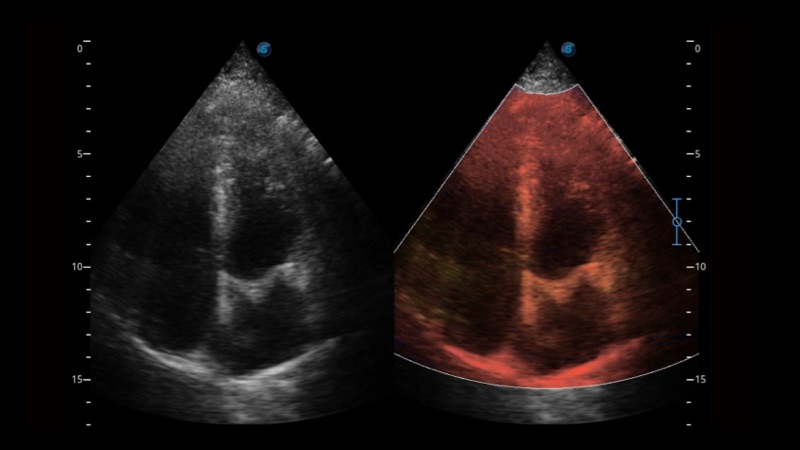

開立醫(yī)療通過不斷的技術(shù)創(chuàng)新,為大眾的生命健康提供持續(xù)關(guān)愛。P12 Plus采用全新一代超聲成像平臺,新平臺旨在將真實(shí)還原組織解剖結(jié)構(gòu)作為首要目標(biāo)。平臺采用全新集成化硬件模塊,搭載新一代芯片,系統(tǒng)性能得到大幅提升,為您的診斷提供了豐富的臨床信息。優(yōu)異的圖像表現(xiàn),豐富的探頭配置,全面的應(yīng)用功能,為您日常診斷提供了可靠的助手。

P12 Plus

彩色多普勒超聲診斷系統(tǒng)